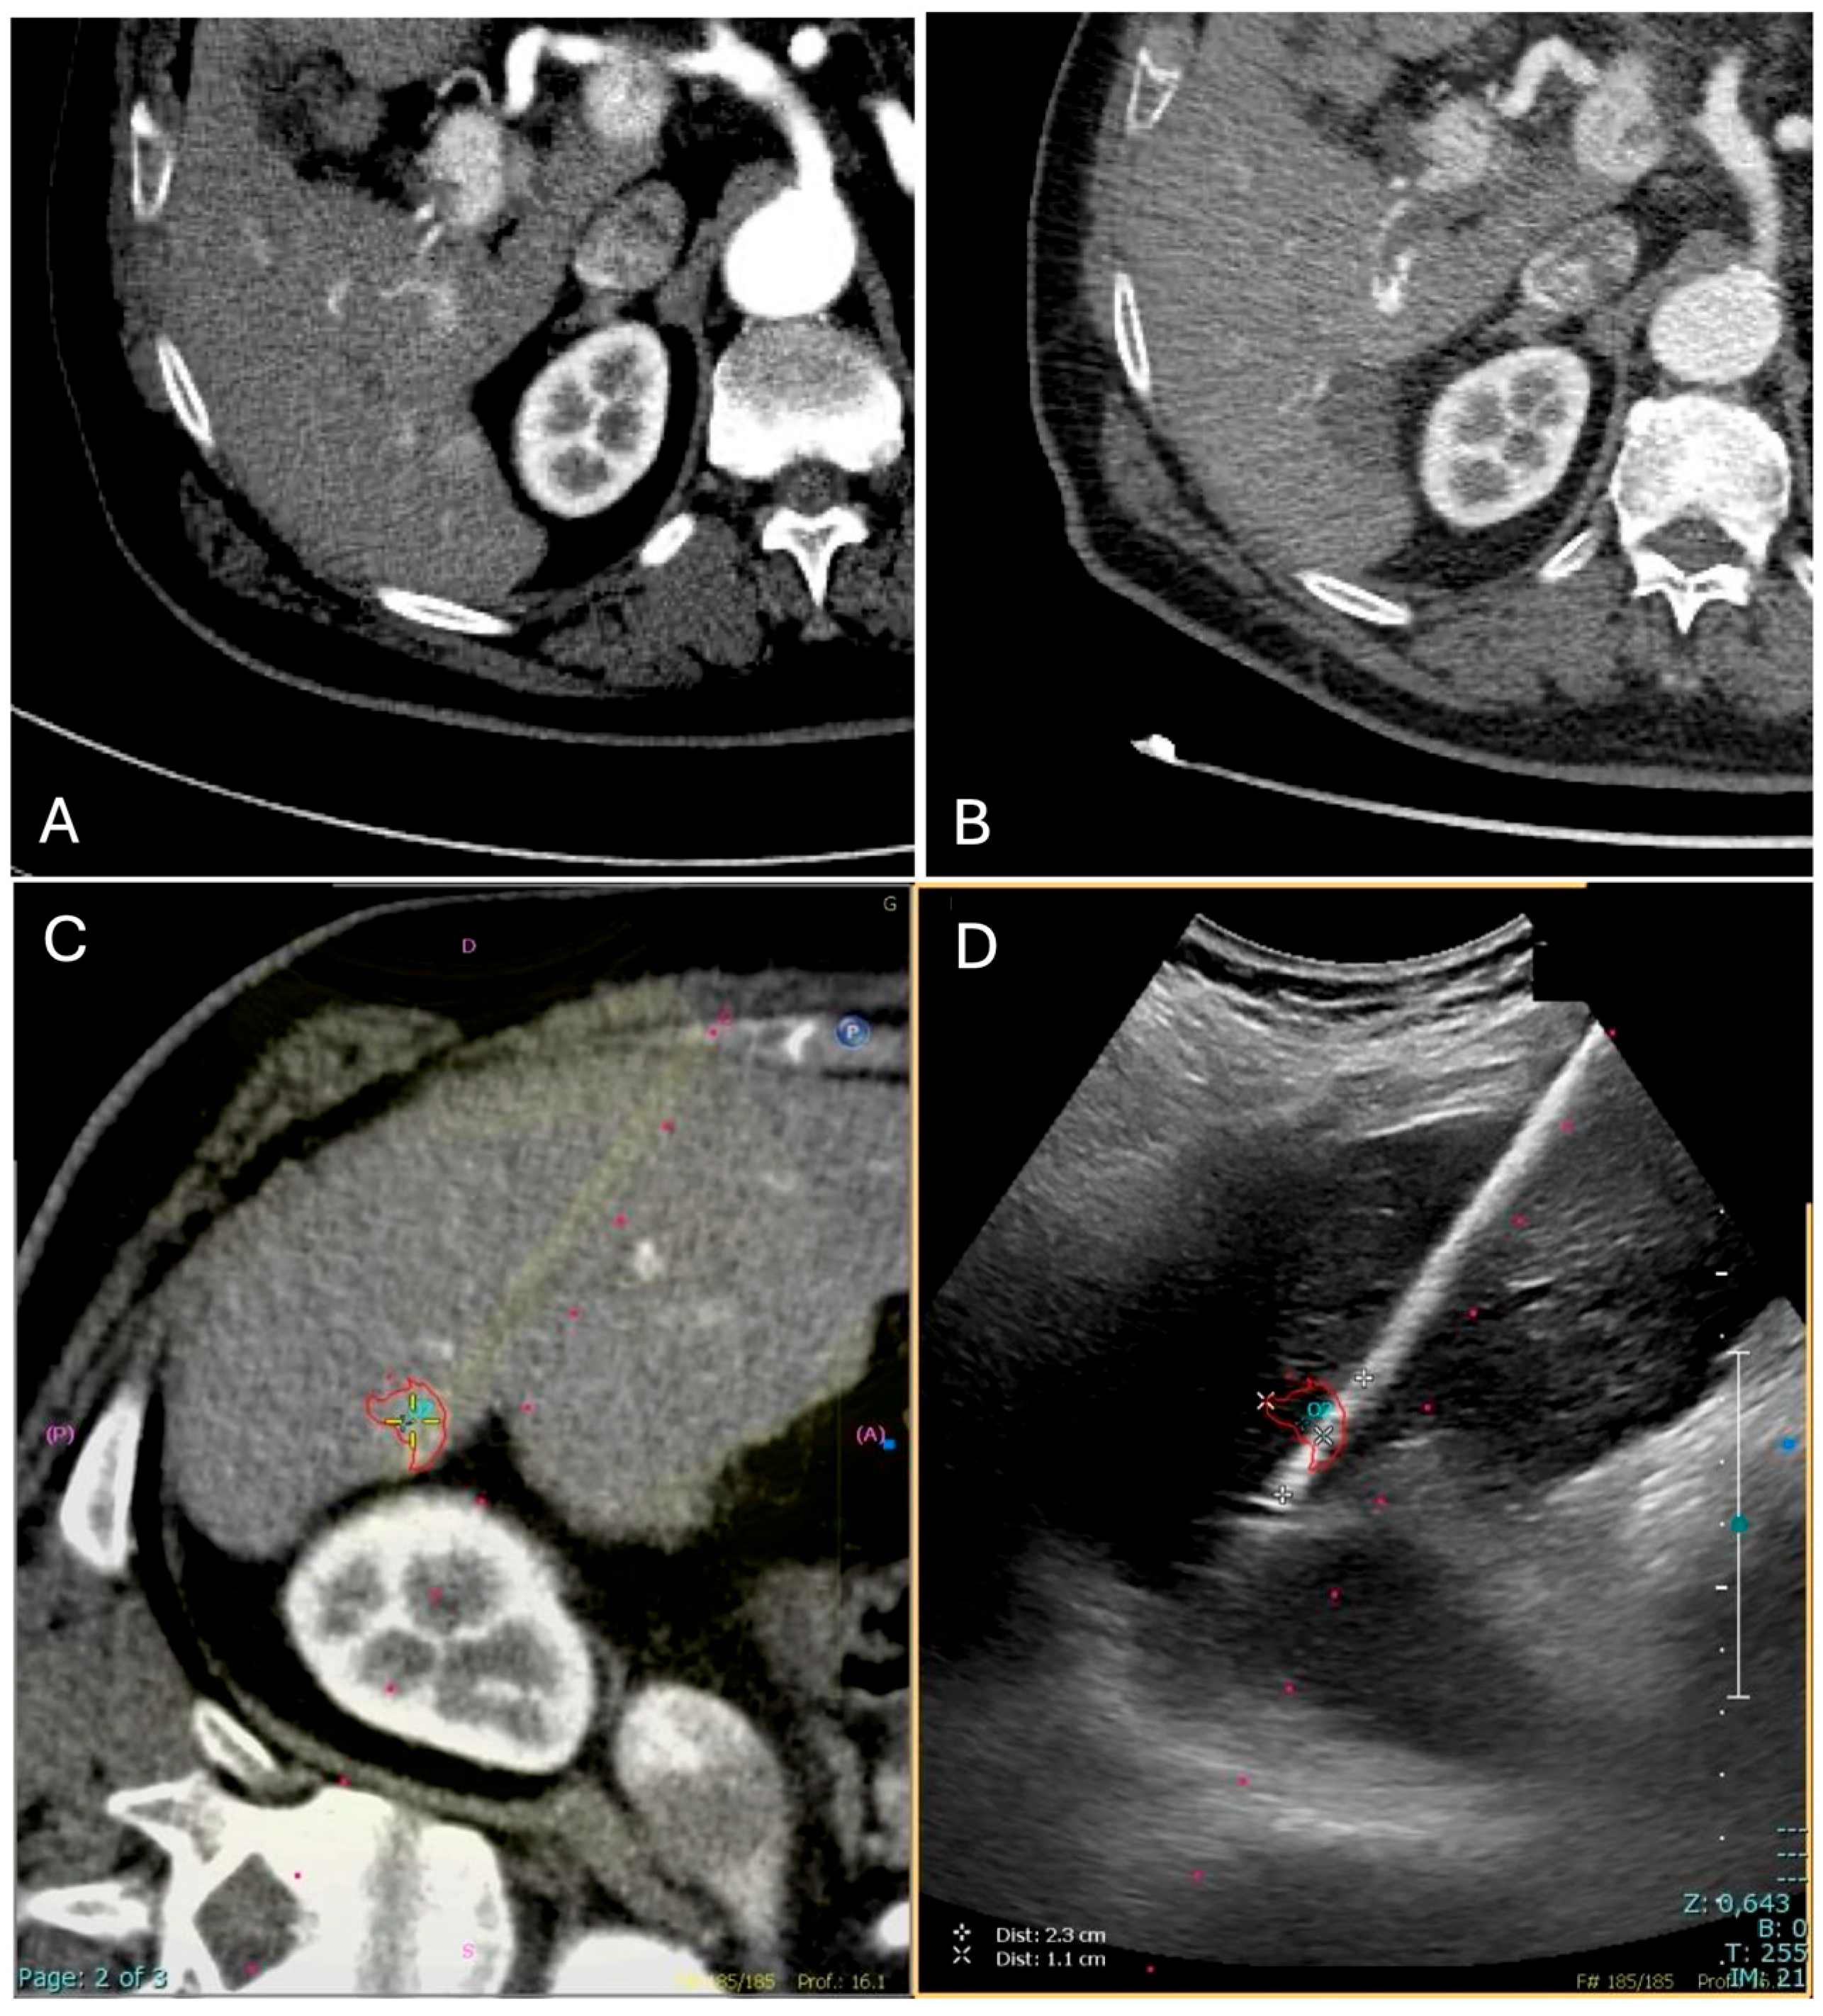

Fusion imaging was performed with electromagnetic tracking using automatic vessel registration via dedicated software (PercuNav System, Software vers. 7.0.8, Philips Medical Systems, Netherlands).The process involves acquiring an ultrasound scan of the liver to create a 3D dataset registered by a software to cross-sectional images based on the hepatic vessels (Figure 1). If automatic registration was not judged adequate, some manual adjustments were performed.

Figure 1. Image fusion workflow for percutaneous ablation planning. After co-registration of pre-procedural CT images with real-time ultrasound (US), the integrated display includes: fused CT–US images with the US superimposed on the CT images (A), real-time US alone (B), CT images alone (C), and 3D position of the US probe (D). The target lesion is highlighted with a pink circle, aiding in precise localization for intervention.